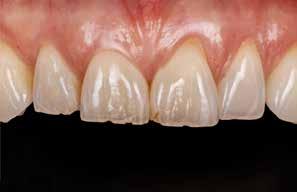

I samråd med patienten og egen tandlæge* afstemmes forventningerne, inden der bestilles refinement alignere. Nivelleringen af alle tænder i tandbuerne, smilelinje og -kurve samt den bukko-lingvale position af incisiverne foretages og efterfølges af retainers lingvalt på over- og underkæbeincisiver (Fig. 3 A-D). Hele behandlingen udføres under løbende kommunikation med patient og egen tandlæge*, der udfører den efterfølgende rekonstruktion med direkte plast (Fig. 4 A-D). Behandlingsvarigheden har været to år og to måneder, hvor ortodontien har forløbet over 21 måneder. Der har været anvendt et første sæt på 66 alignere samt yderligere to sæt med ni refinement alignere. Tandblegning og direkte plastrekonstruktion er udført af egen tandlæge* (Fig. 5 A-F).

Fig. 5. A, B. Smil og kæbeforhold før og efter. Et bredere smil med korrektion af de laterale mørke rum. C-F. Harmonisk hældning af overkæbe- og underkæbeincisiver, rekonstruktion af den tabte tandsubstans efter nivellering af gingivaniveau og optimal bukko-lingval placering til direkte plastbehandling.

5. A, B. Smile and jaw relationships before and after. A wider smile with correction of the lateral dark spaces. C-F. Harmonious inclination of the upper and lower jaw incisors, reconstruction of the lost tooth substance after leveling the gingival level, and optimal bucco-lingual positioning for direct plastic treatment.